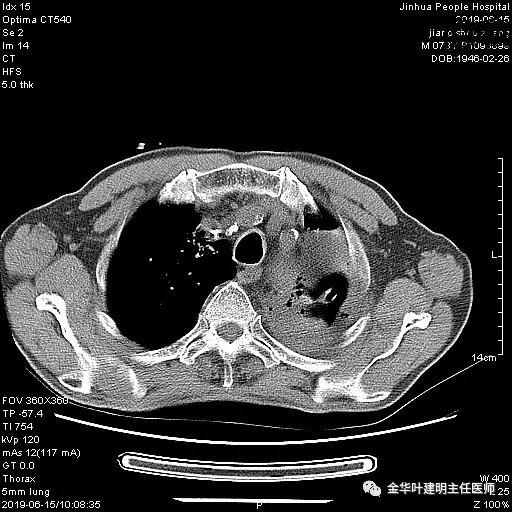

6.15上午:24小时胸管引流出血性液250ml;复查胸部CT示: